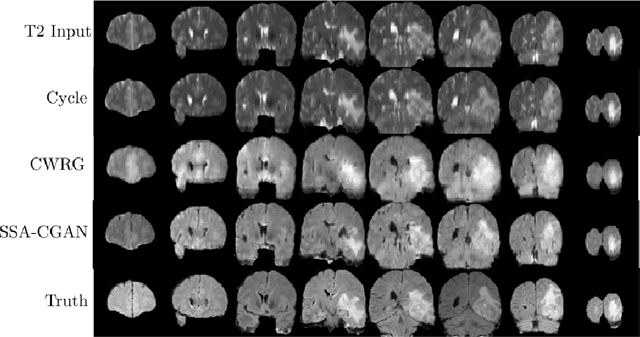

Magnetic Resonance Imaging (MRI) of the brain can come in the form of different modalities such as T1-weighted and Fluid Attenuated Inversion Recovery (FLAIR) which has been used to investigate a wide range of neurological disorders. Current state-of-the-art models for brain tissue segmentation and disease classification require multiple modalities for training and inference. However, the acquisition of all of these modalities are expensive, time-consuming, inconvenient and the required modalities are often not available. As a result, these datasets contain large amounts of \emph{unpaired} data, where examples in the dataset do not contain all modalities. On the other hand, there is smaller fraction of examples that contain all modalities (\emph{paired} data) and furthermore each modality is high dimensional when compared to number of datapoints. In this work, we develop a method to address these issues with semi-supervised learning in translating between two neuroimaging modalities. Our proposed model, Semi-Supervised Adversarial CycleGAN (SSA-CGAN), uses an adversarial loss to learn from \emph{unpaired} data points, cycle loss to enforce consistent reconstructions of the mappings and another adversarial loss to take advantage of \emph{paired} data points. Our experiments demonstrate that our proposed framework produces an improvement in reconstruction error and reduced variance for the pairwise translation of multiple modalities and is more robust to thermal noise when compared to existing methods.